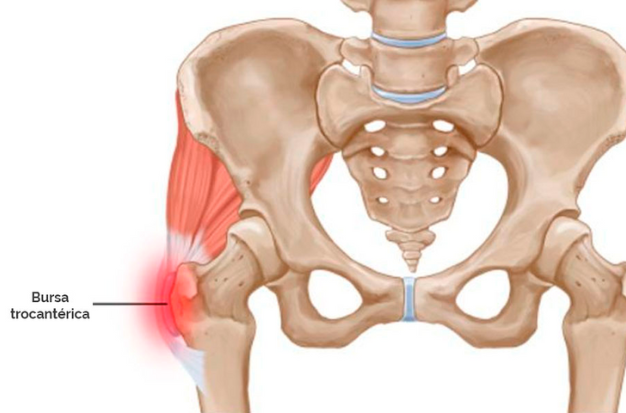

La trocanteritis, también conocida como bursitis trocantérica, es una inflamación de la bursa situada sobre el trocánter mayor, una prominencia ósea ubicada en la parte lateral de la cadera. Esta bursa actúa como un amortiguador que reduce la fricción entre los tendones y el hueso.

Cuando se inflama, provoca dolor lateral en la cadera que puede irradiar hacia el muslo y dificultar actividades tan comunes como caminar, sentarse o dormir del lado afectado.